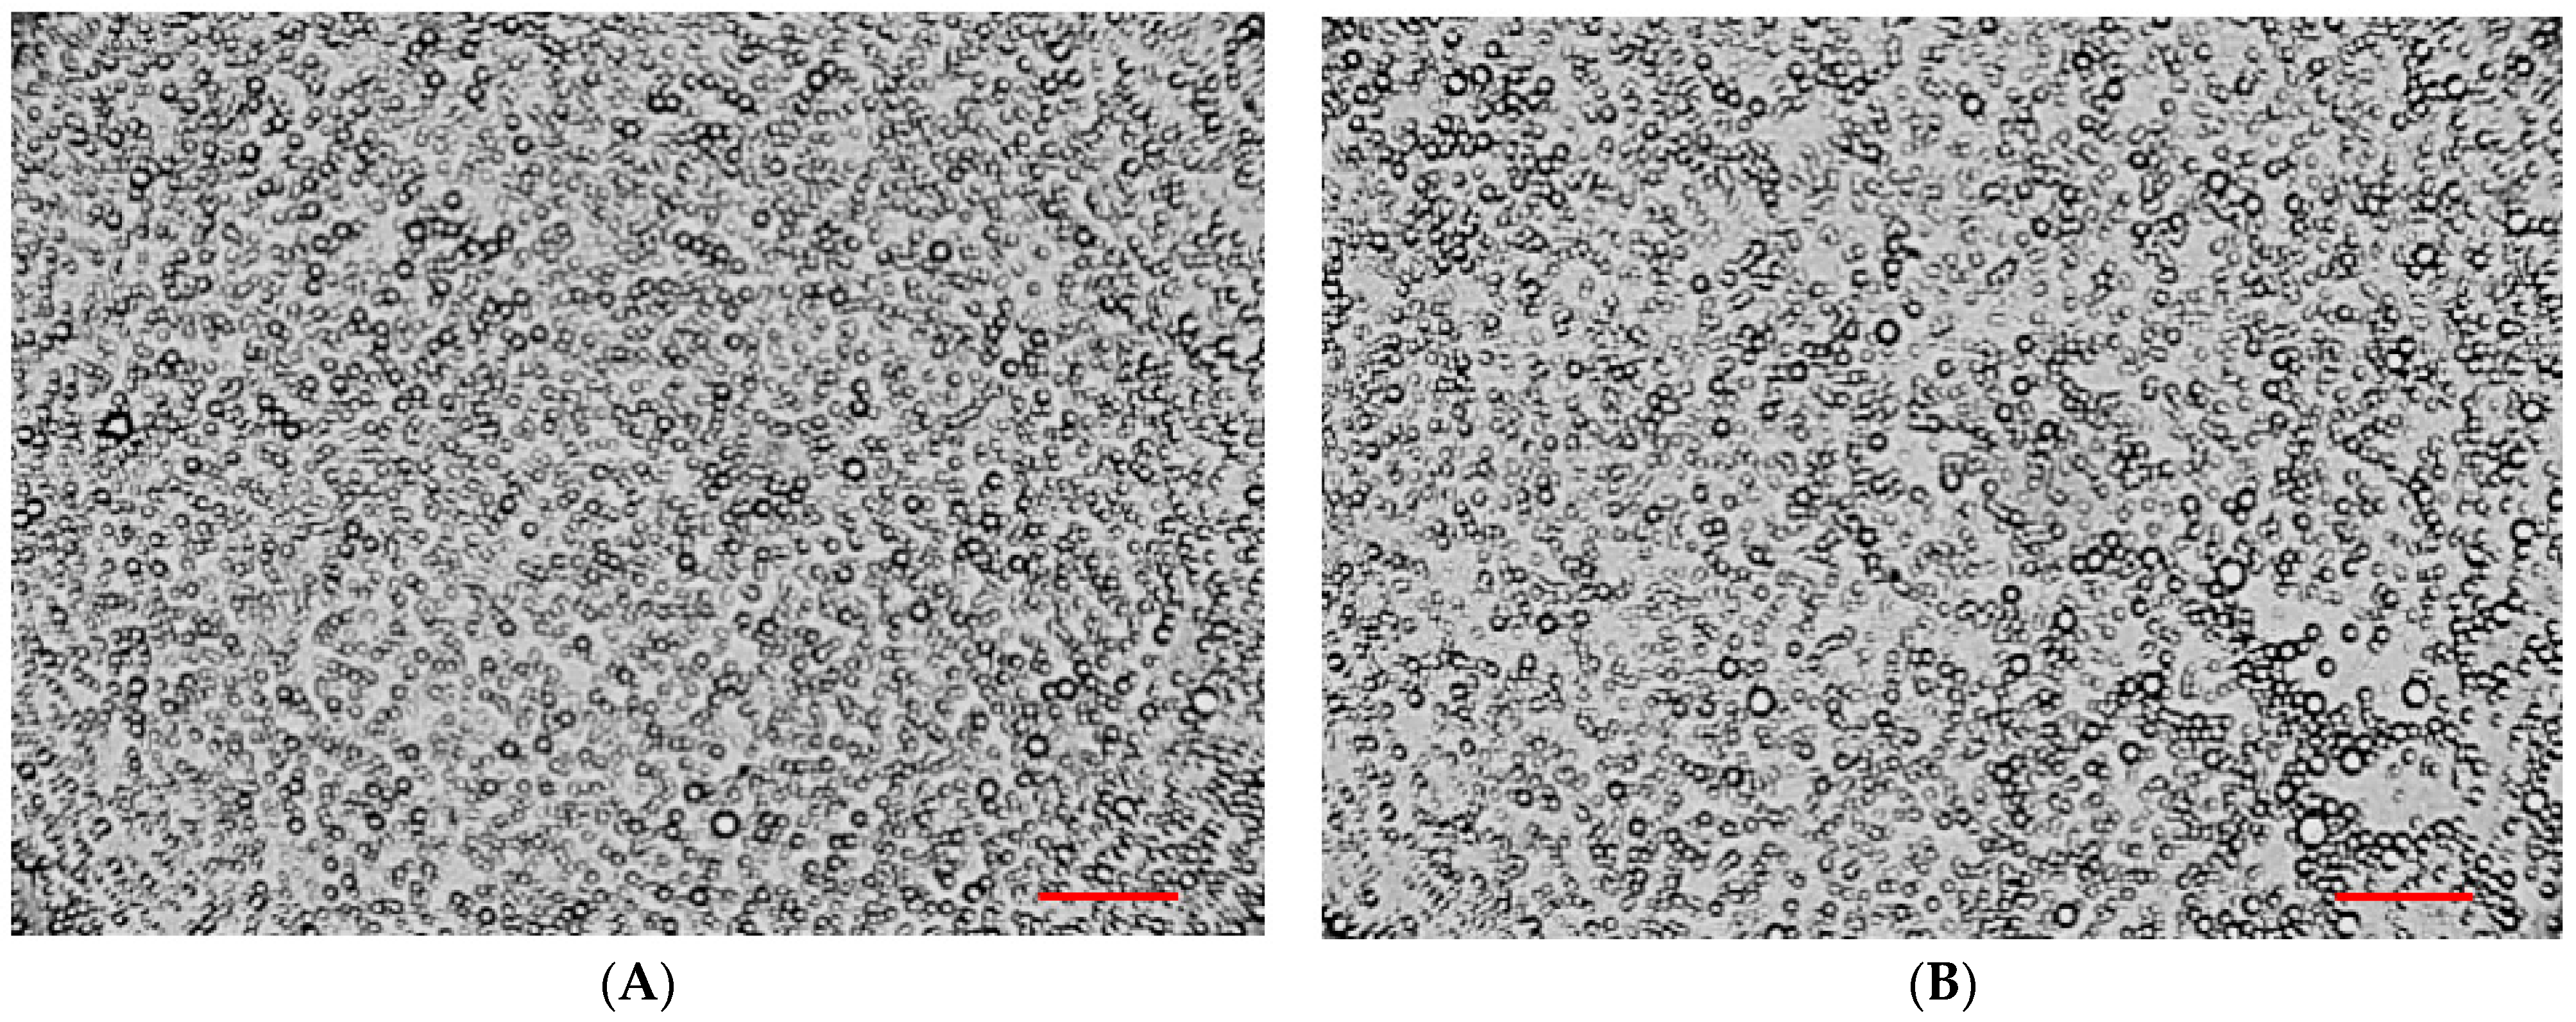

2.4. Microscopic Analysis of the Bigels